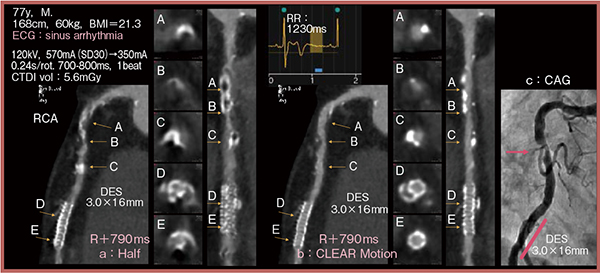

症例3は,77歳,男性。洞不全症候群のため,撮影時に心周期が急速流入期に差しかかってしまい,ハーフ再構成の画像(図4 a)では右冠動脈(RCA)が不明瞭である。一方,CLEAR Motionを適用した画像(図4 b)では,狭窄が疑われる箇所(B)が明瞭に描出されており,ステントの開存性が保たれていることも確認できる。その後行われた冠動脈造影(CAG:図4 c)でも,CLEAR Motionの画像と一致する箇所(→)に狭窄が認められた。

図4 症例3:洞不全症候群